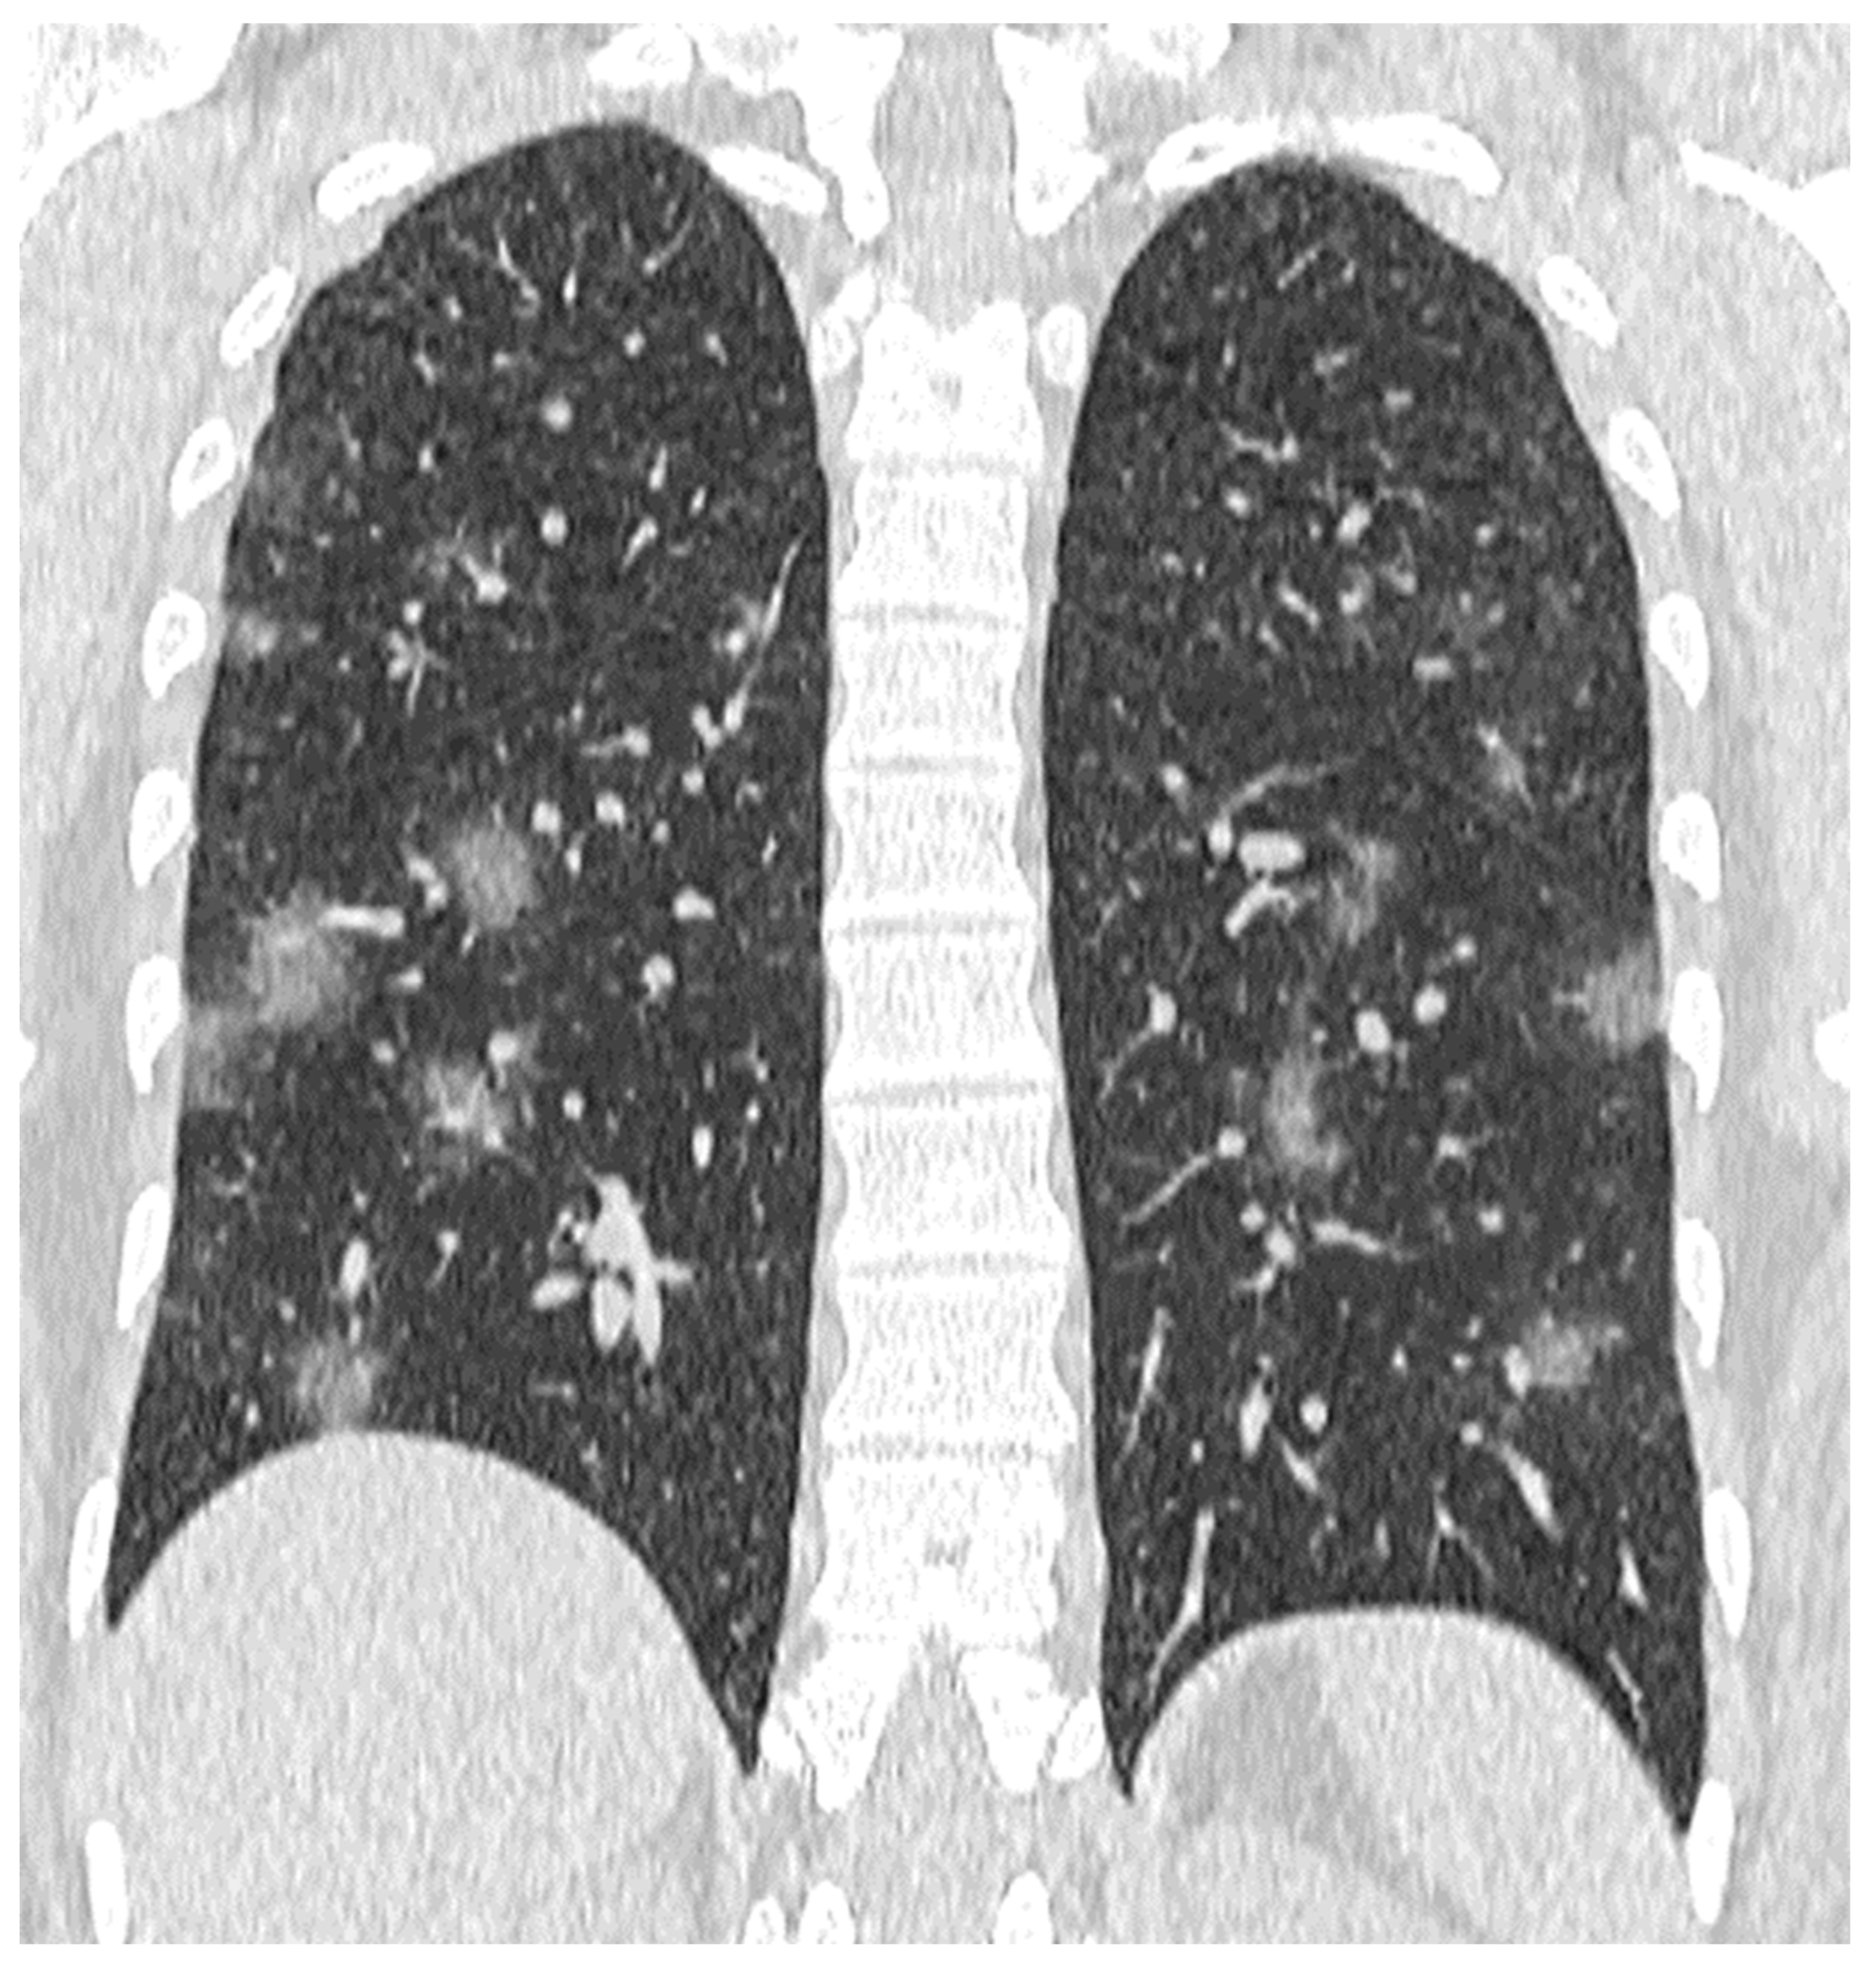

- Crazy paving pattern: thickened interlobular septa and intralobular lines superimposed on a background of ground glass opacity (Figure 5);